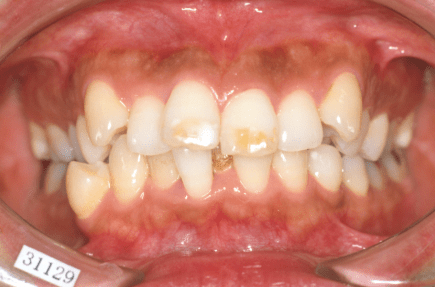

叢生(デコボコ)

原因:歯の大きさと顎の骨の横幅のアンバランス

叢生(そうせい)の原因とは?

一般的には、一つ一つの歯の大きさと顎の骨の大きさとのバランスが悪いことが叢生の原因とされております。